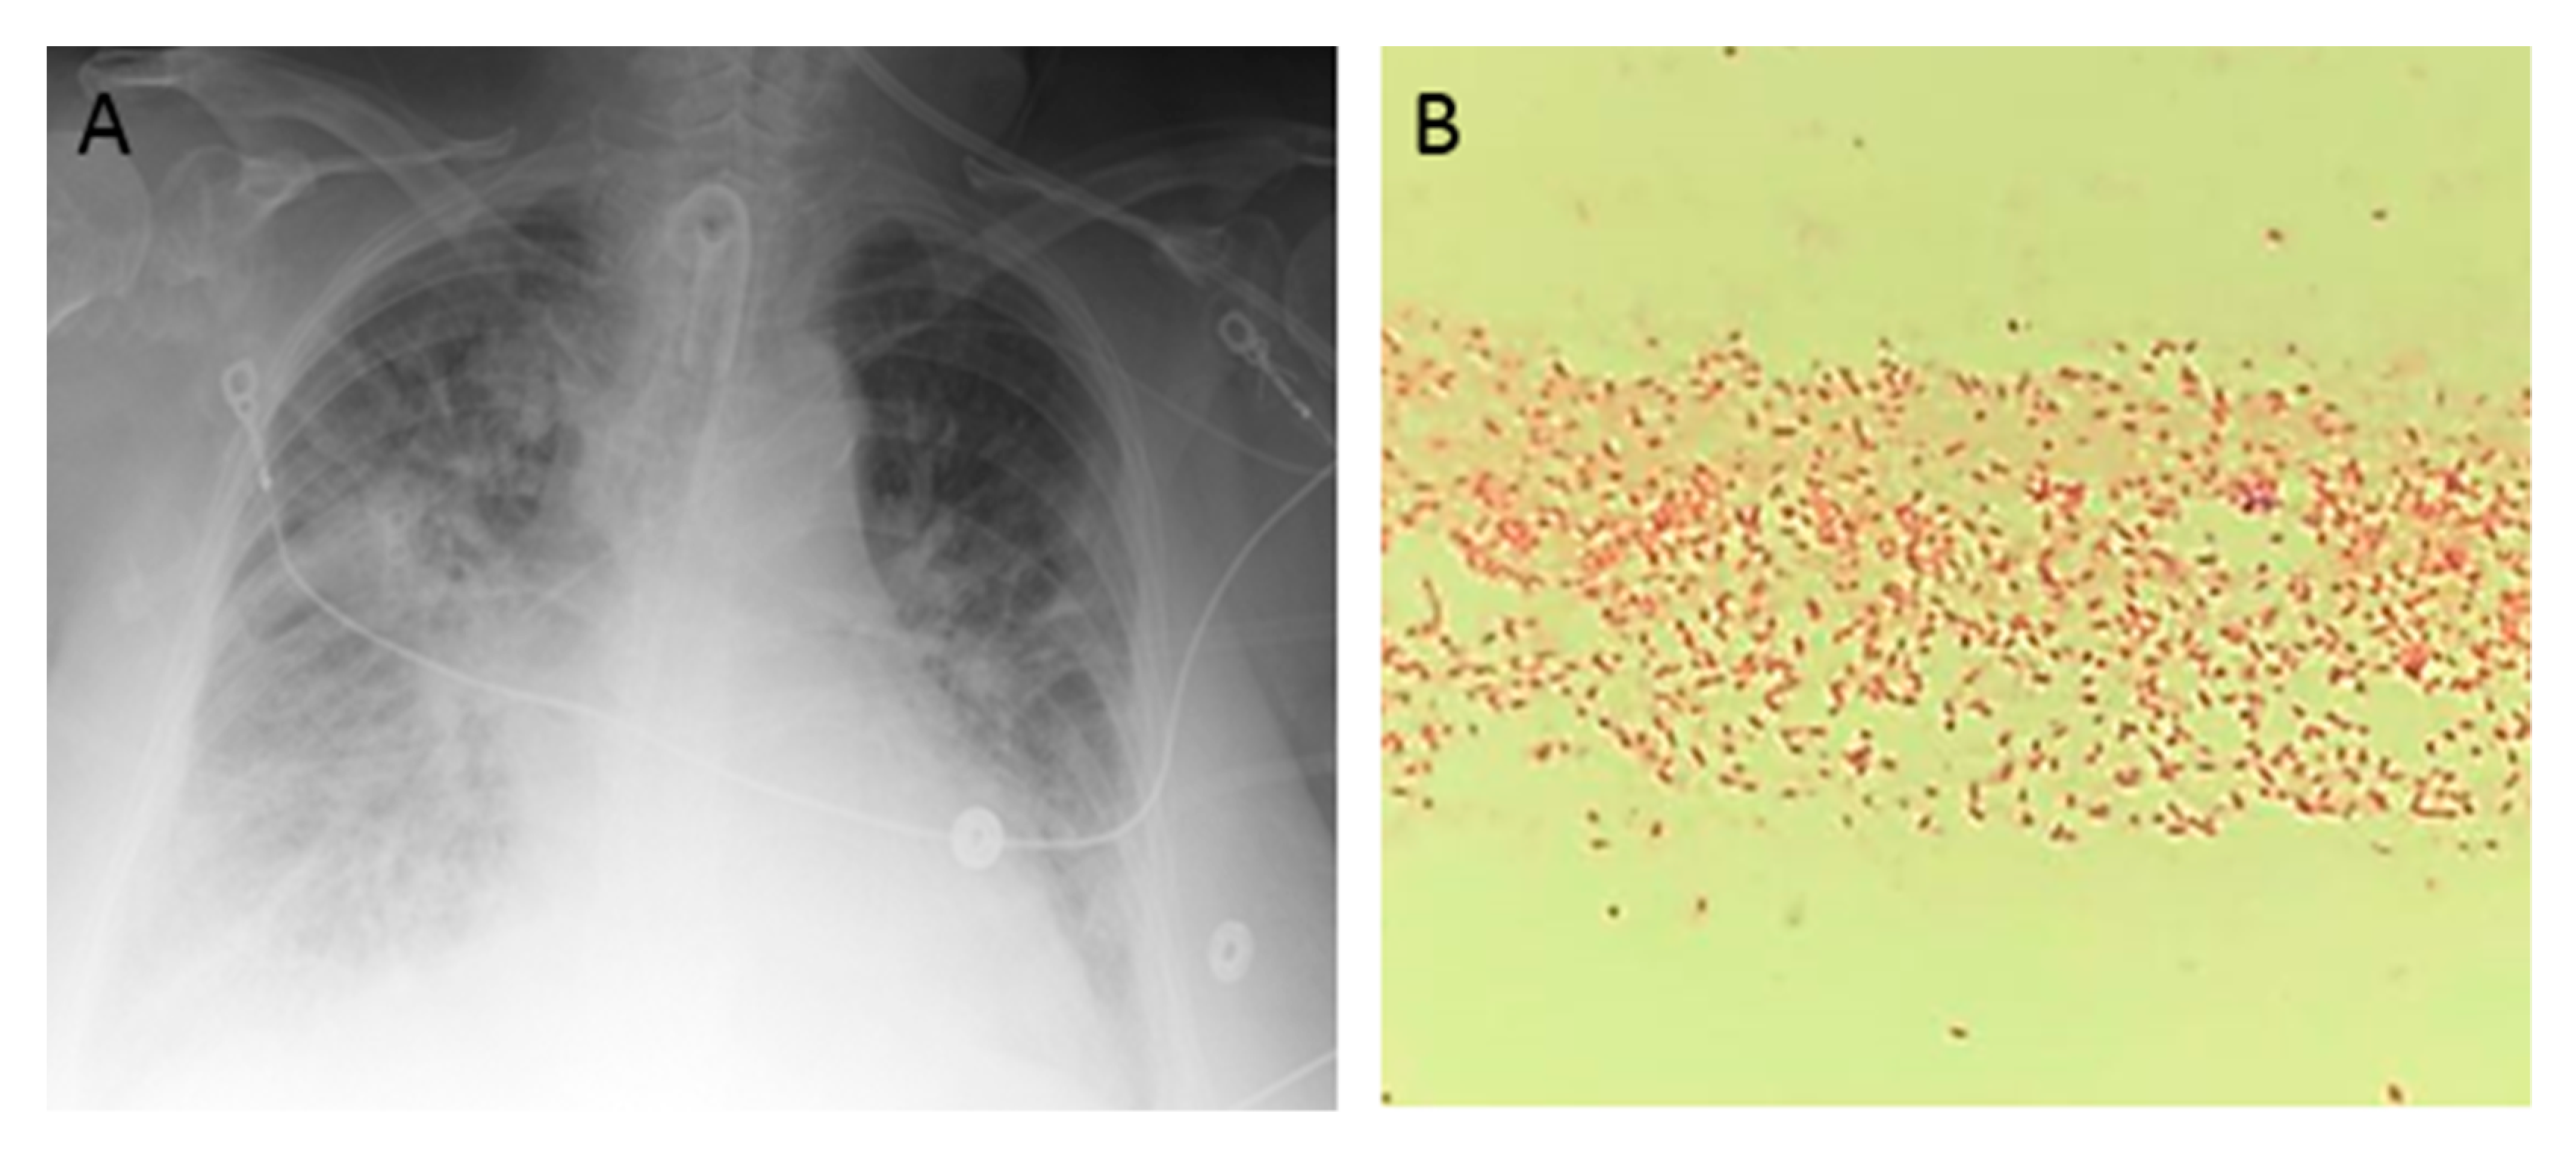

An 85-year-old woman presented to the hospital after sustaining burn injuries and smoke exposure from a house fire. On admission, she was tachypneic, with a respiratory rate of 20 breaths per minute. Her physical exam was significant for 2nd degree burns along the dorsal and palmar aspects of her first three fingers on the right hand and partially on the index finger and thumb of her left hand. She had 1st degree burns on the rest of her hands and both forearms, as well as on the entire face and neck. Her wounds were debrided and silvedene was applied on her hands and forearms, while bacitracin was used for her face. Shortly after admission, the patient experienced difficulty breathing, trouble swallowing, voice changes and swelling around her mouth and tongue. She was intubated for airway protection and was transferred to the intensive care unit (ICU). She was extubated 2 days later, but re-intubated after an episode of projectile vomiting and aspiration. Due to the development of fevers, blood and urine cultures were taken. She was started on cefepime 2 g every 12 h and vancomycin 15 mg/kg every 12 h for aspiration pneumonia. Blood culture grew methicillin-sensitive Staphylococcus aureus and urine culture was positive for Morganella morganii. Four days later, she developed spontaneous pneumothorax that required chest tube placement. Persistence of fever and worsening leukocytosis prompted antibiotic escalation to meropenem with continuation of vancomycin. Over the next 2 days, the patient developed acute renal failure and was started on continuous veno-venous hemodialysis. She completed 12 days of antibiotics. Over the next week, she developed a central line bloodstream infection caused by Enterococcus faecalis and ventilator associated pneumonia caused by methicillin-sensitive Staphylococcus aureus, for which she was treated with ampicillin/sulbactam for 7 days. Three days later, the patient developed a new episode of fever and worsening bilateral infiltrates in chest X-ray (A). Cultures were obtained, and gram stain from blood culture and endotracheal aspirate revealed gram-negative bacilli (B). The Mac Conckey agar demonstrated a pink color, which is characteristic of lactose-fermenting organisms (C). The patient was started empirically on cefepime 2 g every 12 h, and the central lines were removed (one of the potential sources of infection). The gram-negative rod was identified as Raoultella planticola by MALDI-TOF (matrix-assisted laser desorption ionization time of flight), and further in-vitro susceptibility testing by the Vitek® 2 system (BioMérieux, Inc., Hazelwood, MO, USA) revealed resistance to most antibiotics, except for colistin, polymyxin B, aminoglycosides, tetracycline, and tigecycline (D). We performed additional phenotypic tests and detected carbapenemase production by the Carbapenem Inactivation Method (E). Supplementary antibiotic susceptibility studies by E-test showed susceptibility to ceftazidime/avibactam (F, left side) and meropenem/vaborbactam (F, right side). Confirmation of carbapenemase production was carried out by genotypic analysis using Verigene system (Luminex Corp, Austin, TX, USA), which identified blaKPC and blaCTX-M genes. Treatment with cefepime was discontinued and the patient was started on combination therapy with ceftazidime/avibactam and polymyxin B. Follow-up blood cultures were negative and her respiratory status improved over the following days. Finally, she was transferred to a LTAC (long-term acute care) facility to complete 2 weeks of antibiotic therapy.